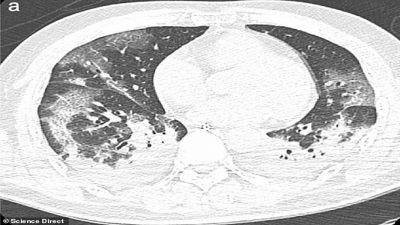

Los especialistas del Instituto Nacional de Enfermedades Infecciosas en Roma estudiaron los cuerpos de los pacientes de 65 y 67 años y detectaron, mediante rayos-X y tomografías computarizadas, un gran deterioro en la función de los pulmones.

Cuando coronavirus ataca los pulmones, provoca una inflamación en las membranas mucosas, lo genera un daño en los alvéolos pulmonares, que tienen que trabajar más para suministrar oxígeno a la sangre que circula por todo el cuerpo y eliminar el dióxido de carbono para que se pueda exhalar. La inflamación y el daño al flujo de oxígeno pueden causar que dichas áreas en los pulmones se llenen de fluido, pus y células muertas.